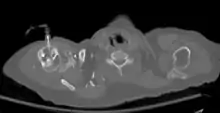

The needle is injected through the bone's hard cortex and into the soft marrow interior which allows immediate access to the vascular system. The IO needle is positioned at a 90 degree angle to the injection site, and the needle is advanced through manual traction, impact driven force, or power driven.[8] Each IO device has different designated insertion locations. The most common site of insertion is the antero-medial aspect of the upper, proximal tibia as it lies just under the skin and is easily located. This is on the upper and inner portion of the tibia. Other insertion sites include the anterior aspect of the femur, the superior iliac crest, proximal humerus, proximal tibia, distal tibia, sternum (manubrium).[9]